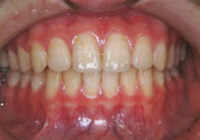

症例4:上顎前突(出っ歯)

治療前

治療後